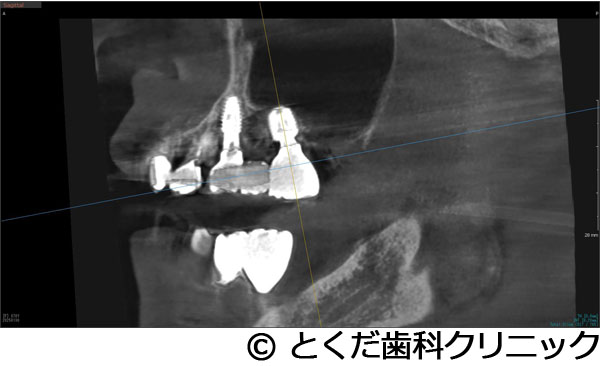

¡Ú¾ÉÎã3¡Ûº¸¾å5¤ÎËË¡¦À妤ÎÂçÉý¤Ê¹ü·ç»¤¬¤¢¤ê¡¢¤«¤Ä¡¢¾å³ÜƶÄì¤Þ¤Ç3mmÄøÅ٤δû¸¹ü¤·¤«¤Ê¤¤¾ÉÎ㤬¡¢¼£ÎÅ´ü´Ö2.5¥õ·î¤Ç¼£ÎŤ¬½ª¤ï¤Ã¤¿¥±¡¼¥¹

- º¸¾å5¤ÎËË¡¦À妤ÎÂçÉý¤Ê¹ü·ç»¤¬¤¢¤ê¡¢¤«¤Ä¡¢¾å³ÜƶÄì¤Þ¤Ç3mmÄøÅ٤δû¸¹ü¤·¤«¤Ê¤¤¾ÉÎ㤬¡¢¼£ÎÅ´ü´Ö2.5¥õ·î¤Ç¼£ÎŤ¬½ª¤ï¤Ã¤¿¥±¡¼¥¹

¼£ÎÅÊýË¡

´µ¼ÔÍͤ¬º¸¾å5¤ÎÇÓÇ¿¤ò¼çÁʤËÍ象¡¢¾Ã±ê¸å¤ËÈ´»õ¤ò´õ˾¤·¤¿¤¿¤áÈ´»õ¤ò¹Ô¤¤¤Þ¤·¤¿¡£¤½¤Î¸å¡¢´µ¼ÔÍͤ¬¥¤¥ó¥×¥é¥ó¥È¼£ÎŤò´õ˾¤·¤¿¤¿¤áÈ´»õ¸å¡¢¼þ°ÏÁÈ¿¥¤¬°ÂÄꤹ¤ë¤Î¤òÂԤäƥ¤¥ó¥×¥é¥ó¥È¼ê½Ñ¤ò¹Ô¤Ã¤Æ¤¤¤Þ¤¹¡£ÆâÍÆ¤Ï¡¢¾å³Ü´û¸¹ü¤¬Çö¤¤¤¿¤á¥°¥é¥Õ¥È¥ì¥¹¥µ¥¤¥Ê¥¹¥ê¥Õ¥È¤ÈʹԤ·¤Æ¡¢¹ü¤¬ÂçÉý¤Ë·ç»¤·¤¿Éôʬ¤Ø¤Î¹üÊäŶºÞŶÆþ¤ò¹Ô¤¤1²óË¡¤Ç¼ê½Ñ¤ò´°Î»¤·¡¢9½µ¸å¤Ë¸÷³Ø°õ¾Ý¤Ç°õ¾Ý¤ò¹Ô¤¤¡¢¥¸¥ë¥³¥Ë¥¢¤ÎºÇ½ªÊäÄÖʪ¤ò11½µ¤ÇÁõÃ夷¤Æ¼£ÎŤò´°Î»¤·¤Æ¤¤¤Þ¤¹¡£

ÂçÉý¤Ê¹ü·ç»¤¬¤¢¤Ã¤¿¤¬¡¢¥°¥é¥Õ¥È¥ì¥¹¥µ¥¤¥Ê¥¹¥ê¥Õ¥È¤È¹ü·ç»Éô¤Ë¿Í¹©¹ü¤òÊäŶ¤·¤Æ¡¢¤ï¤º¤«2¥õ·îȾ¤Ç¼£ÎŤò´°Î»¤¹¤ë¤³¤È¤¬¤Ç¤¤¿¡Ê²¾¤Ë¡¢GBR¤äÄ̾ï¤Î¥µ¥¤¥Ê¥¹¥ê¥Õ¥È¤ò¹Ô¤¤¼£ÎŤò¹Ô¤Ã¤Æ¤¤¤¿¤é¡¢ºÇÄã¤Ç¤â1ǯ¤Ï¤«¤«¤ë¥±¡¼¥¹¤Ç¤¹¡Ë¡£Ä㿯½±¤Ç¡¢Ã»»þ´Ö¤Ç¡¢¼£ÎŤò½ª¤¨¤ë¤³¤È¤¬¤Ç¤¡¢¤Þ¤¿¡¢¿³ÈþÀ¡¦µ¡Ç½À¤Î²óÉü¤â¹Ô¤¦¤³¤È¤¬¤Ç¤¤¿¡£